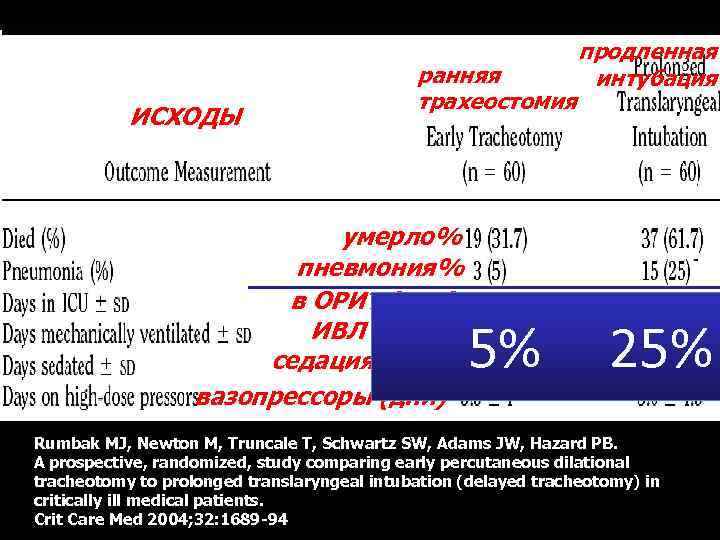

ИСХОДЫ ранняя трахеостомия продленная интубация умерло% пневмония% в ОРИТ (дни) ИВЛ (дни) седация (дни) вазопрессоры (дни) Rumbak MJ, Newton M, Truncale T, Schwartz SW, Adams JW, Hazard PB. A prospective, randomized, study comparing early percutaneous dilational tracheotomy to prolonged translaryngeal intubation (delayed tracheotomy) in critically ill medical patients. Crit Care Med 2004; 32: 1689 -94

ИСХОДЫ ранняя трахеостомия продленная интубация умерло% пневмония% в ОРИТ (дни) ИВЛ (дни) седация (дни) вазопрессоры (дни) Rumbak MJ, Newton M, Truncale T, Schwartz SW, Adams JW, Hazard PB. A prospective, randomized, study comparing early percutaneous dilational tracheotomy to prolonged translaryngeal intubation (delayed tracheotomy) in critically ill medical patients. Crit Care Med 2004; 32: 1689 -94

ИСХОДЫ ранняя трахеостомия умерло% пневмония% в ОРИТ (дни) ИВЛ (дни) седация (дни) вазопрессоры (дни) продленная интубация 5% 25% Rumbak MJ, Newton M, Truncale T, Schwartz SW, Adams JW, Hazard PB. A prospective, randomized, study comparing early percutaneous dilational tracheotomy to prolonged translaryngeal intubation (delayed tracheotomy) in critically ill medical patients. Crit Care Med 2004; 32: 1689 -94

ИСХОДЫ ранняя трахеостомия умерло% пневмония% в ОРИТ (дни) ИВЛ (дни) седация (дни) вазопрессоры (дни) продленная интубация 5% 25% Rumbak MJ, Newton M, Truncale T, Schwartz SW, Adams JW, Hazard PB. A prospective, randomized, study comparing early percutaneous dilational tracheotomy to prolonged translaryngeal intubation (delayed tracheotomy) in critically ill medical patients. Crit Care Med 2004; 32: 1689 -94

Факторы риска снижать седацию активизация реабилитация

Факторы риска снижать седацию активизация реабилитация

ИСХОДЫ ранняя трахеостомия умерло% пневмония% в ОРИТ (дни) ИВЛ (дни) седация (дни) вазопрессоры (дни) продленная интубация 3, 2 14, 1 Rumbak MJ, Newton M, Truncale T, Schwartz SW, Adams JW, Hazard PB. A prospective, randomized, study comparing early percutaneous dilational tracheotomy to prolonged translaryngeal intubation (delayed tracheotomy) in critically ill medical patients. Crit Care Med 2004; 32: 1689 -94

ИСХОДЫ ранняя трахеостомия умерло% пневмония% в ОРИТ (дни) ИВЛ (дни) седация (дни) вазопрессоры (дни) продленная интубация 3, 2 14, 1 Rumbak MJ, Newton M, Truncale T, Schwartz SW, Adams JW, Hazard PB. A prospective, randomized, study comparing early percutaneous dilational tracheotomy to prolonged translaryngeal intubation (delayed tracheotomy) in critically ill medical patients. Crit Care Med 2004; 32: 1689 -94